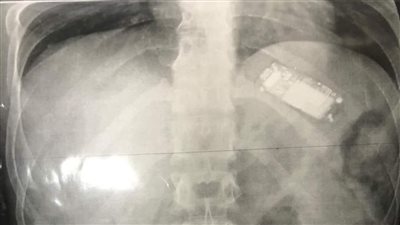

ابتلعه منذ شهرين.. استخراج تليفون محمول من بطن شاب بالمنصورة

تفاصيل استخراج تليفون محمول من بطن سجين بالمنوفية | صور

بنها الجامعي ينجح في استخراج هاتف محمول من معدة شاب بالقليوبية | صور

بلعه بالخطأ.. استخراج “موبايل” من معدة مريض بعد بلعه بـ7 شهور (صور)